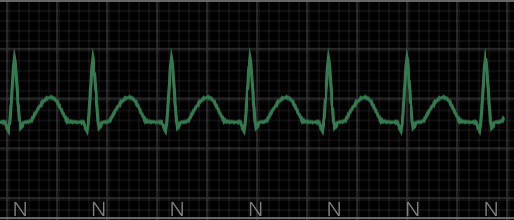

外傷の評価として基本的には「ABCD」を評価

A(Airway):気道

C(Circulation):循環

D(Dysfunction of central nervous system):中枢神経機能異常

今回のように出血が死因につながるような状況では

MARCHという考え方の評価

M(Massive hemorrhage):大量出血

A(Airway):気道

R(Respiratory):呼吸

C(Circulation):循環

H(Hypothermia):低体温、Head injury(頭部外傷)の評価